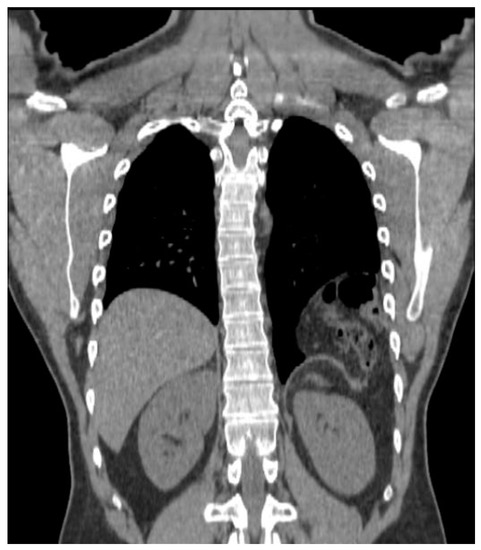

Between 2010 and 2018, the patient experienced increasing dyspnea on exertion and left chest discomfort. In February 2018, a CT showed the persistence of the hernia, which was measured as a 3.3 cm diaphragmatic orifice containing colon and greater omentum, for a total volume estimated at 560 cc (Figure 1 and Figure 2). He underwent preoperative consultation in June 2018, at which he complained of dyspnea, left chest discomfort, as well as occasional constipation. On clinical examination, the patient had scars from left subcostal and midline laparotomy incisions, as well as decreased left basilar breath sounds on chest auscultation.

Figure 2.

3-D reconstruction of the CT-scan performed in 2018 showing the location of the hernia (yellow arrows).